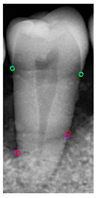

3.3. CEJ and ALC Position Result

Table 11 presents the accuracy of the Mask R-CNN model for three categories, comparing the results from original images with those from enhanced images. The results show that image enhancement had the most significant improvement in the accuracy of the Tooth Mask, increasing from 92.63% to 93.48%. For the Bone Mask, the accuracy slightly improved from 95.50% to 96.95%. However, for the Crown Mask, the accuracy slightly decreased from 96.79% to 96.21% after image enhancement. This indicates that while image enhancement generally has a positive impact on the model’s accuracy, its effects can vary across different mask categories. Table 12 provides a comparative analysis between our developed positioning algorithm and the annotations supplied by the dentist. The upper portion demonstrates the CEJ and ALC levels ascertained by the algorithm, juxtaposed with the dentist’s marked points on both the left and right sides. Specifically, these points encompass CEJ (left) and CEJ (right) for the CEJ level and ALC (left) and ALC (right) for the ALC level. The lower segment portrays a segmented image, showcasing the positions identified by the algorithm in contrast to those identified by the dentist. The blue and purple circles represent the annotations made by the dentist and the red and green circles represent the annotation result of this study. Furthermore, it computes precision in every CEJ and ALC point on both sides, along with determining the Root Mean Square Error (RMSE) between the four points identified by the algorithm and the dentist’s annotations; the RMSE value between different points is lower than 0.09, and the minimum value is 0.0209 in CEJ (right). The RMSE formula is shown in Equation (9).